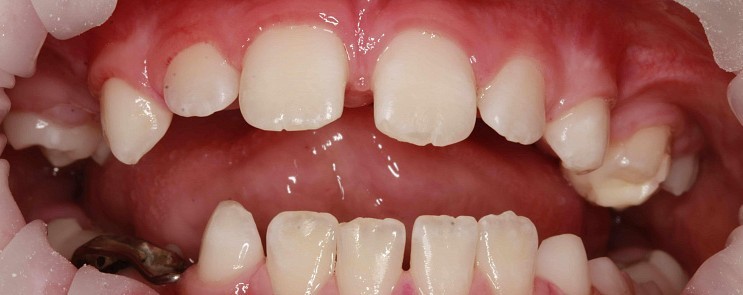

Стоматологическая клиника ЧАСТНАЯ ПРАКТИКА

Чистка зубов Air-flow

Чистка зубов ультразвуком с полировкой. Доктор очень бережно отнесся к сгустку крови образовавшемуся на травмированном камнем участке десны. Это даст возможность максимально быстро восстановиться сосочку десны. Наложенная в дальнейшем лекарственная повязка ускорит процесс.

Доктор: Фалилеев Алексей Константинович